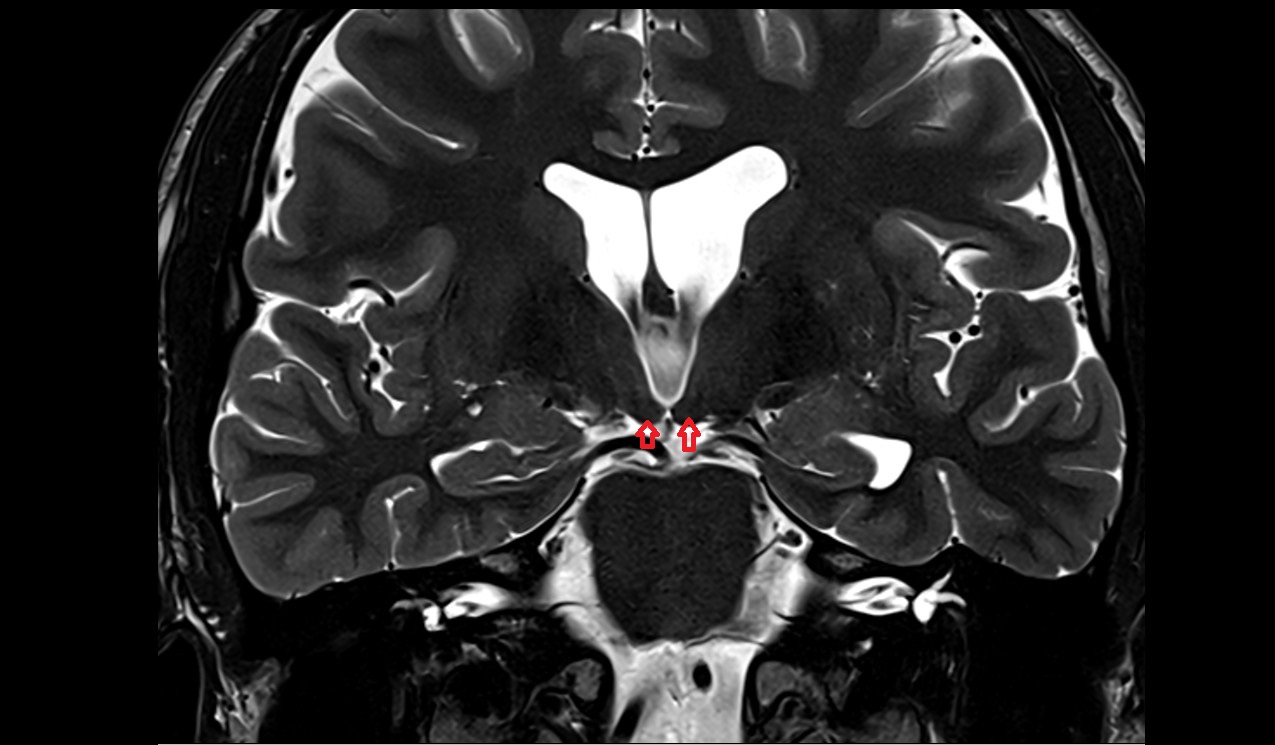

- Optic chiasm

- Pituitary stalk